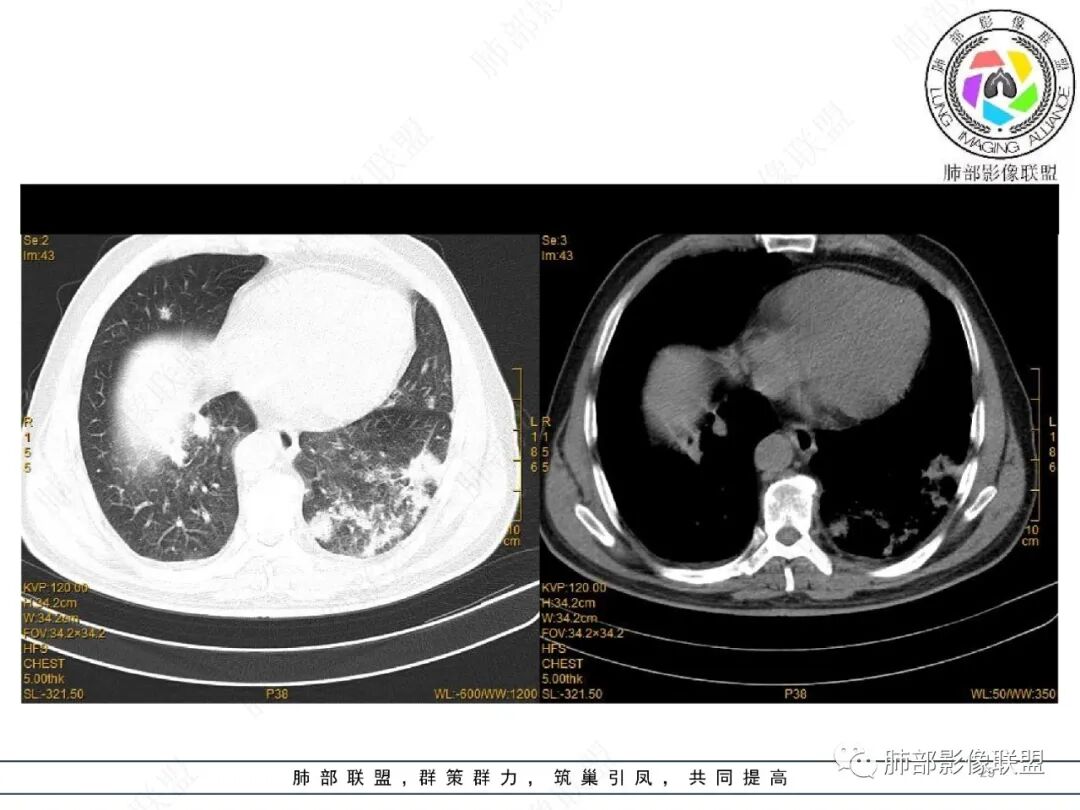

2022.2.17CT显示两肺中内带多发结节影、斑片影、条索影,部分病灶侧向融合与胸膜平行。部分病灶沿着支气管血管束分布、其内支气管稍扩张。部分病灶呈反晕征。大部分病灶边界显示清晰,部分病灶周围可见边界不清的GGO。2022.4.12CT显示两肺中内带多发结节影、条索状、条带状高密度影,边界收缩平直凹陷,大部分病灶沿着支气管血管束分布,亦有位于胸膜下侧向融合与胸膜平行的病灶。总体与第一次CT对比两肺病灶明显吸收。